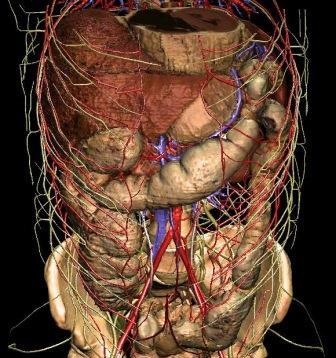

Obținerea secțiuni subțiri vă permite să creați de reconstrucție tridimensională.

Abdomenul este alcătuit din următoarele organe și sisteme:

- Ficat cu căi biliare (intrahepatic duct biliar, duct hepatic comun și vezica biliară cu conducta său);

- pancreas;

- splina;

- tractului gastrointestinal (stomac, intestin subțire și mari);

- ganglionilor limfatici, vaselor de sânge, țesuturi moi ale pereților abdomenului și stomacului.

spațiu retroperitoneal:

- rinichi;

- glandele suprarenale;

- țesut perirenal.